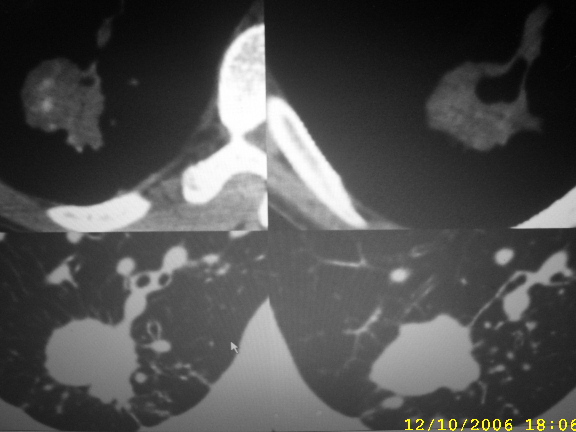

男,44,胸痛,咳嗽月余。

胸片上病灶成条柱状,ct病灶内见钙化影,可见分叶与毛刺和胸膜凹陷征,考虑1感染病变[结核或炎性假瘤]。2肺癌。建议结合临床及进一步检查[如穿刺活检]

除看到分叶、毛刺、空洞外.不知钙化该如何解释!